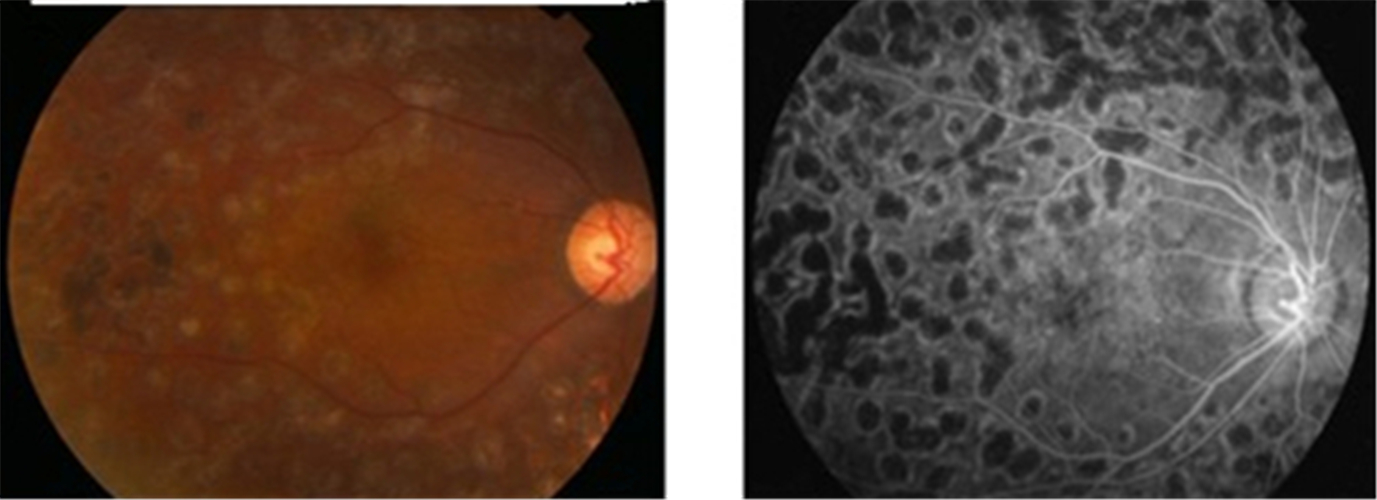

增值引發視網膜脫落

增值併發視網膜脫落

增生引起視網膜脫落

增生併發視網膜脫落

糖尿病人視網膜脫落